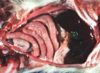

This is a picture of a rumen. What lesion is shown here?

Acute, multifocal to coalescing ulcerative ruminitis